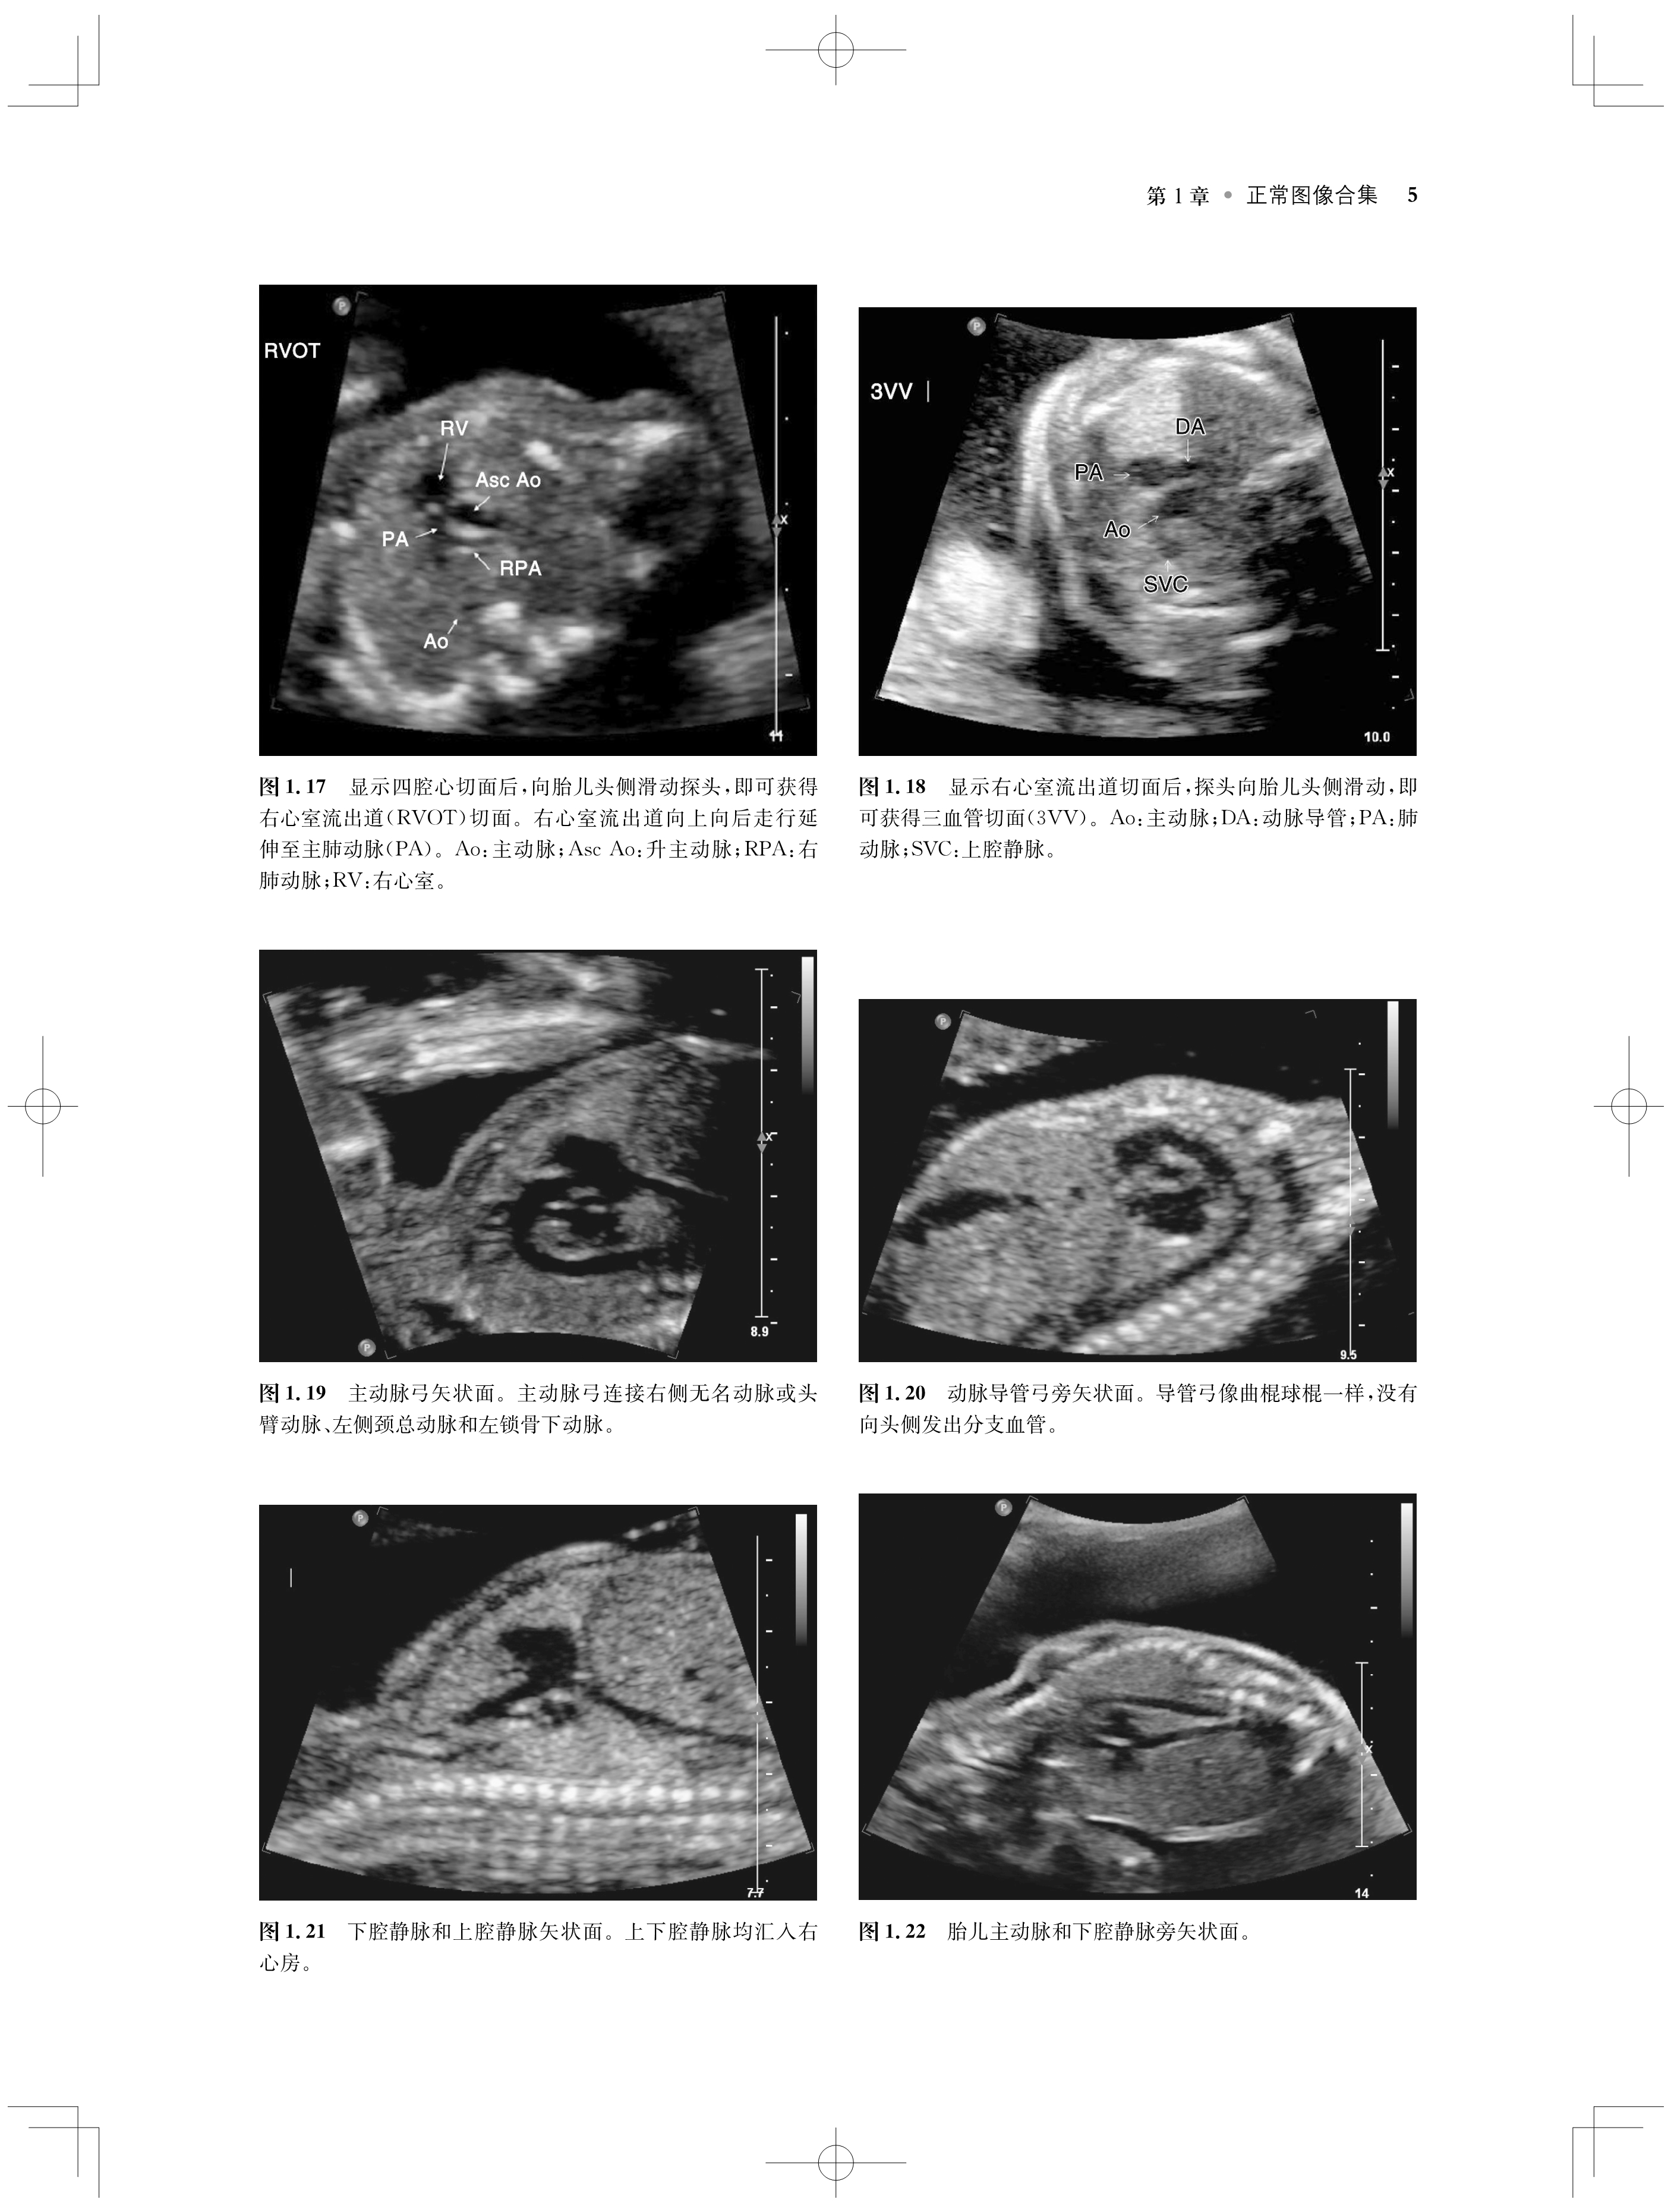

内容涵盖了胎儿宫内疾病的所有病种,从疾病的概述、流行病学、病因学、病理生理学,到临床表现、各类影像学技术的诊断和鉴别诊断,再到产前、产后的治疗和干预手段,都做了全面介绍,重点阐述了疾病的超声、X线、CT、MRI、PET、CT等影像学表现,以及诊断与鉴别诊断,并辅以大量标准化的影像学图片,图文并茂。

《产科影像学——胎儿诊断和监护》是Elsevier(Saunders)出版的“Expert Series”之一,由国际最顶尖的妇产科、生殖科、母胎医学和影像学专家共同编写,代表着该领域最顶尖的水平。书中配有大量典型影像图片,内容丰富全面,编写理念先进,侧重于疾病的影像学征象分析及鉴别诊断和诊断流程的制定,从临床思维上进行了更新;同时兼顾临床和病理医师,重点内容以列表、提要、要点的形式进行总结,提纲挈领,方便读者阅读、记忆。对于每天不断进行诊断与鉴别胎儿疾病的影像工作者、病理科和临床医师而言,具有重要的参考价值。